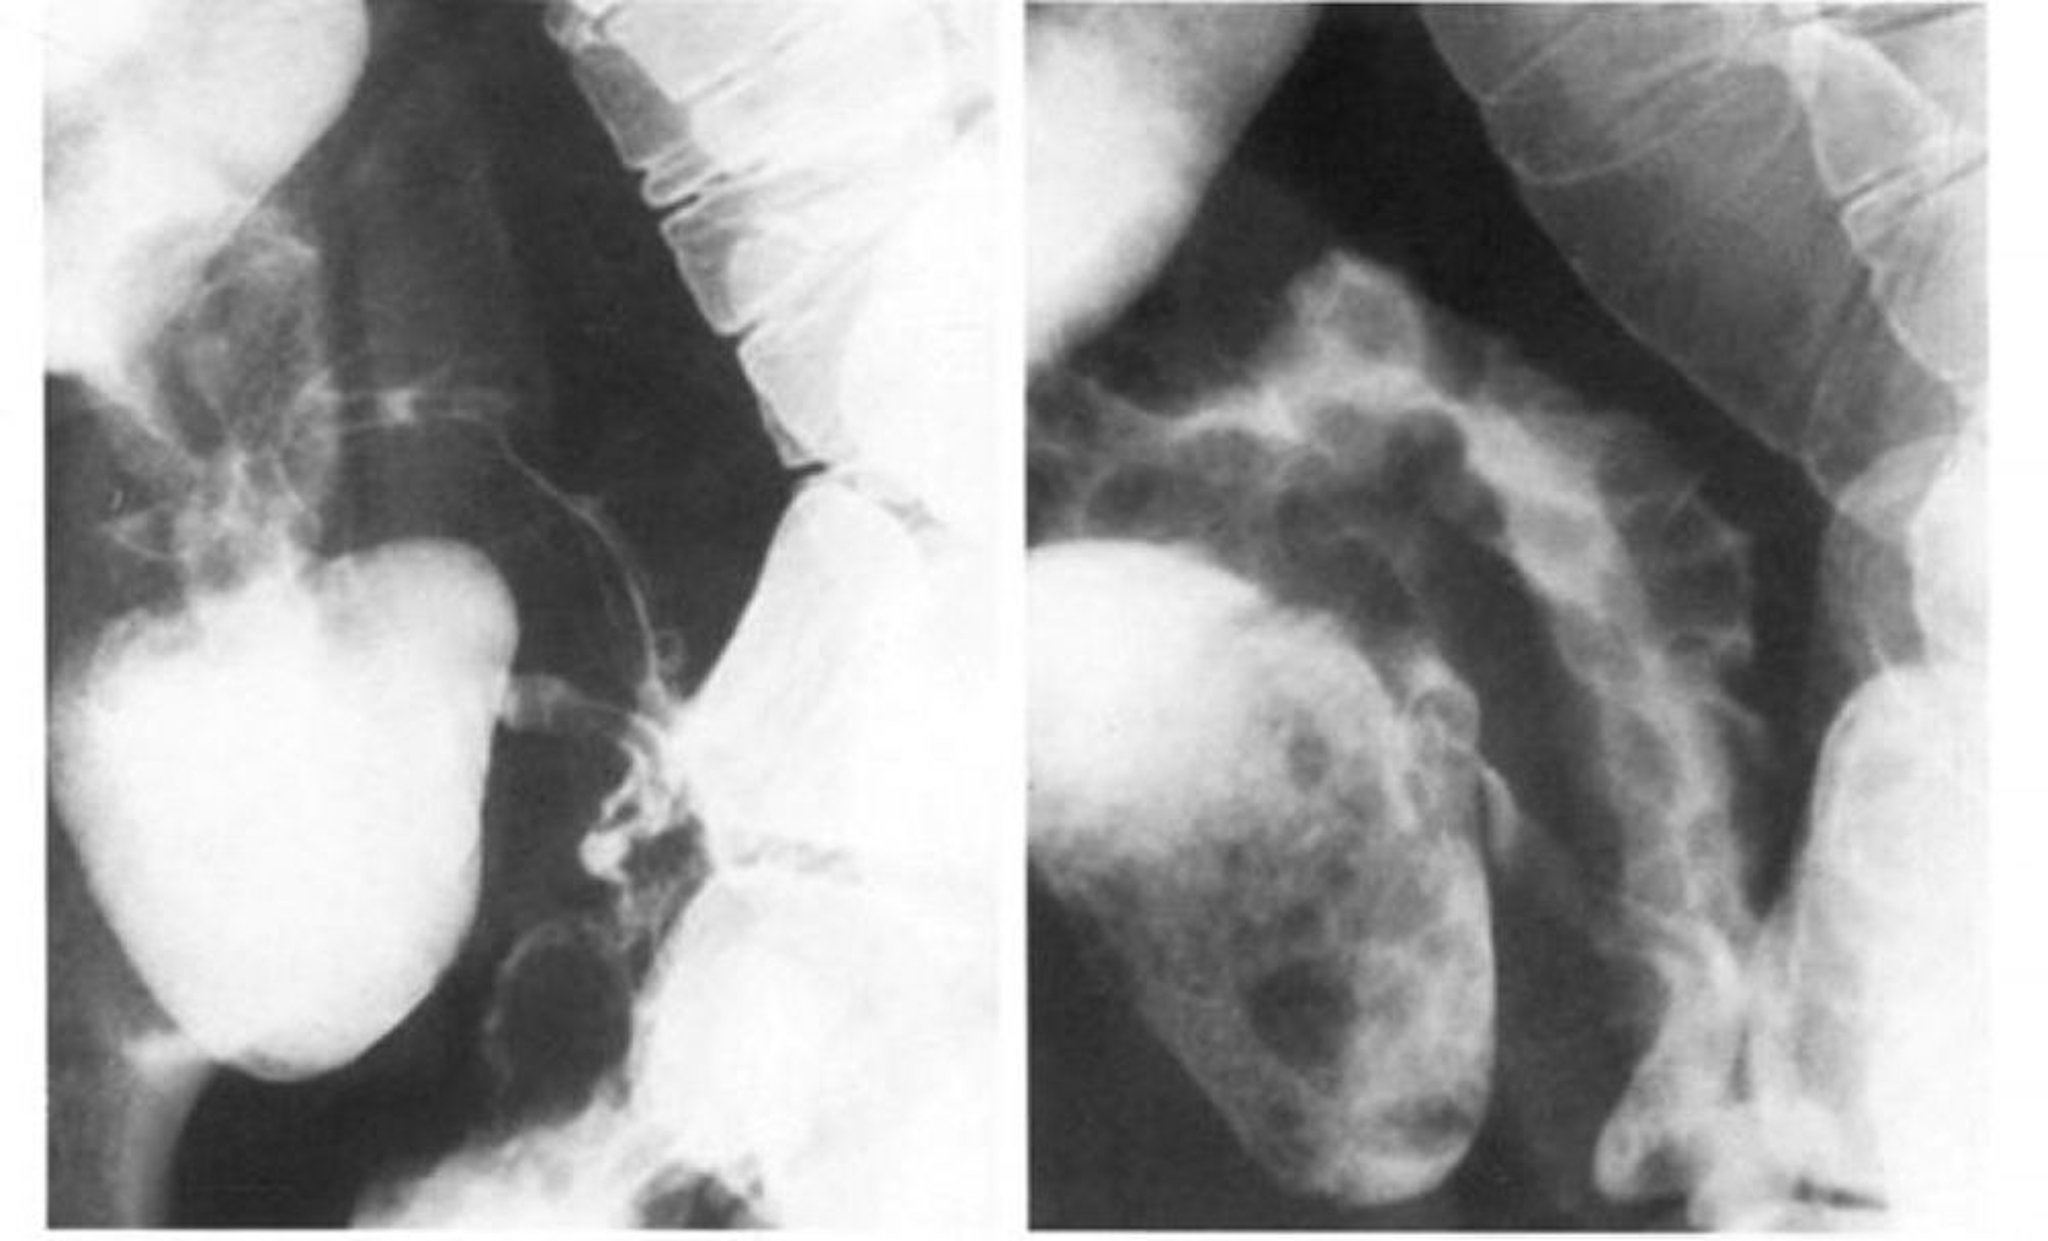

Пассаж бария по тонкой кишке при подозрении на болезнь Крона: "симптом шнура"

На левом изображении видна облитерация терминального отдела подвздошной кишки по типу "булыжной мостовой", которая лучше всего видна при двойном контрастировании на изображении справа.